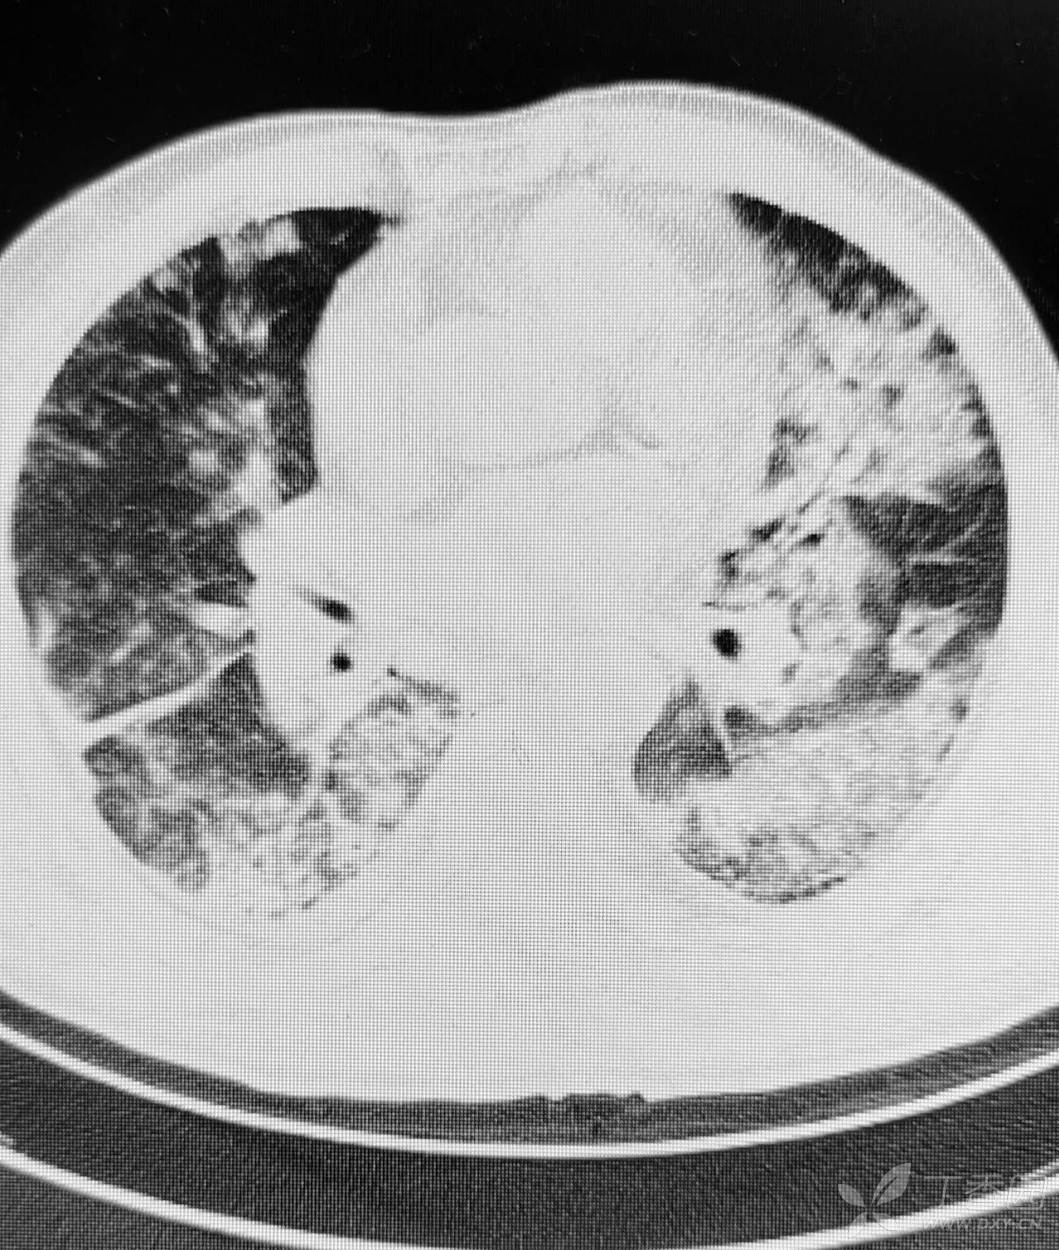

直肠癌术后两个月,接受放化疗一个月。白细胞危急值。

停化疗放疗,升白药物。白细胞增高了。

血小板仍低,血红蛋白开始降低。

胸部影像如图。

目前有血培养阳性,病原菌难以命中。痰培养阳性。